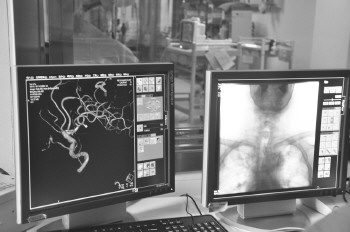

通俗来讲,就是先将显影剂注入血管,利用仪器“绘制”患者血管图,然后在血管内建立通道,随后一根特殊的细管子进入通道“按图索骥”找到血栓后将血栓打碎取出,整个手术过程实现可视化。

介入血管外科学科建设结构合理,具有专业病房和专业的导管手术室。病房有32张床位,具有专业医师团队和护理团队,包括手术和腔内诊治医生10名,专业护理人员16名,其中硕士生导师1人,正教授1人、副教授1人,博士2人、另2人博士在读,其余全部具有硕士研究生学历。介入导管室具有四个手术间,其中两个个手术间达到百万级的净化,可以进行手术和腔内杂交技术治疗血管外科疾病,近几年手术量快速增长,目前年手术量在2500台左右。该手术间应用目前最先进的DSA血管造影机,可三维旋转和后处理实现血管的三维重建功能。提高了介入血管外科疾病的精细诊治水平。科室还配备先进监护设备可进行患者术前、术中、术后血流动力学检测,保证患者的手术安全和治疗效果。